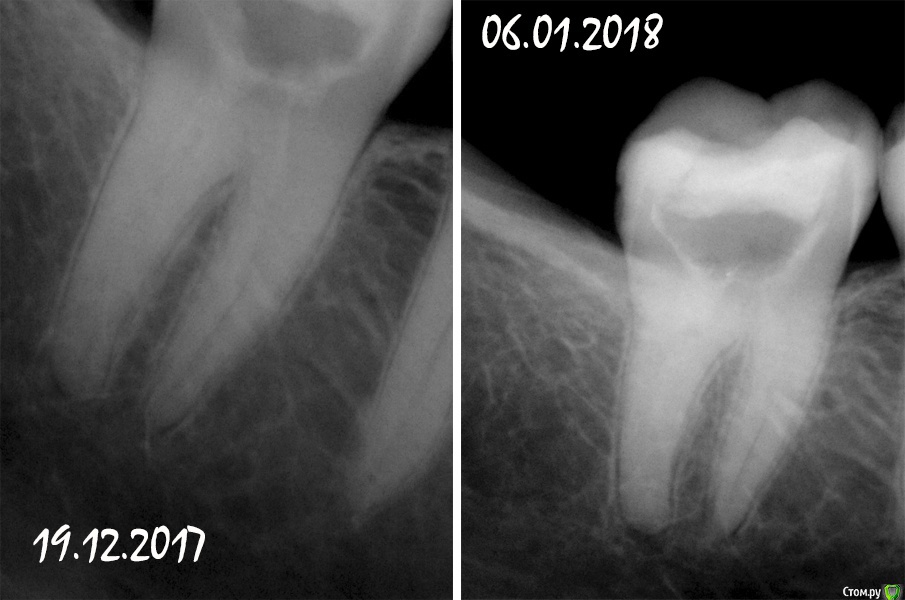

Fatality Опубликовано 7 января, 2018 Автор Поделиться Опубликовано 7 января, 2018 Уважаемые врачи, ищу вашей помощи! У меня нет никаких улучшений со стороны зуба - болит при накусывании, болят стенки при постукивании по ним. Каналы чистили и мыли 4 раза два разных специалиста.13 и 19 декабря после промывки закладывали Каласепт,4 января вскрыли зуб, прочистили и заложили хлоргексидин гель (была нарушена герметичность временной пломбы и врач решил, что в зубе могли начать размножаться грибы Кандида),6 января убрали хлоргексидин и снова положили Каласепт. Мне делали 2 снимка на протяжении лечения, но комментариев по поводу ситуации никто толком не дает. Единственное, сказали, что в коронке зуба появилась трещина, но не знают, дошла ли она до корня. Последний врач сказал, что если воспаление и болевые ощущения не будут проходить, то зуб придется удалить. Я не знаю как нужно поступить в данной ситуации - если нет улучшения в ходе лечения и зуб удалить, либо стоит бороться за зуб и продолжать с периодичностью раз в две недели закладывать лекарство до улучшения ситуации? Пожалуйста, расшифруйте снимки - у меня ощущение, что около корня увеличилось затемнение. Ссылка на комментарий

dok1 Опубликовано 8 января, 2018 Поделиться Опубликовано 8 января, 2018 У вас неполная механическая обработка каналов. Соответственно страдает антисептическая обработка и полнота заполнения временным материалом. Ищите специалиста, который "пройдёт" каналы полностью. Ссылка на комментарий